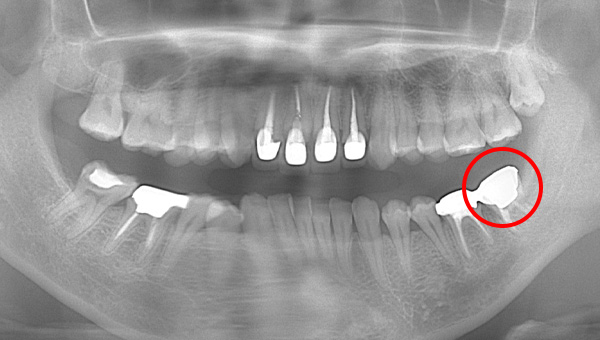

2022.7.9 経過観察後

口腔内写真

レントゲン写真

根管治療後3ヶ月です。根のまわりの骨がやや白くなってきているのがわかります。だんだん骨の添加がみられている証拠になります。

ここまで治癒していればかぶせ物をかぶせても問題ないと判断しました。

2022.10.16 予後経過

1年後 2023.3 予後経過

移植した歯はしっかり機能しており、問題なく使用できているとのことである。

最後のレントゲンでは、骨がしっかり添加され、周囲組織となんら変色ない状態にまでなっていることがわかる。